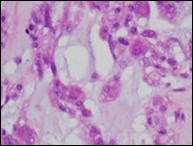

Figure 3.Parachordoma exemplifying clusters and nests of spherical, vacuolated cells with abundant, acidophilic cytoplasm, regular nuclei and an enveloping cartilaginous stroma 14.